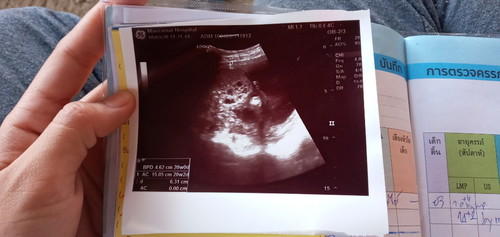

ในรูปจะเห็นเหมือนมีฟองอากาศวงกลมๆ เเต่พอหมอใหญ่ดูเขาก็บอกว่าไม่เป็นอะไรปกติ แต่ก็ยังไม่สบายใจ ยังงี้เราต้องไปอัลตราซาวที่อื่นดูไหมค่ะ เเต่นัดซาวดูอีกทีวันที่21/4/63